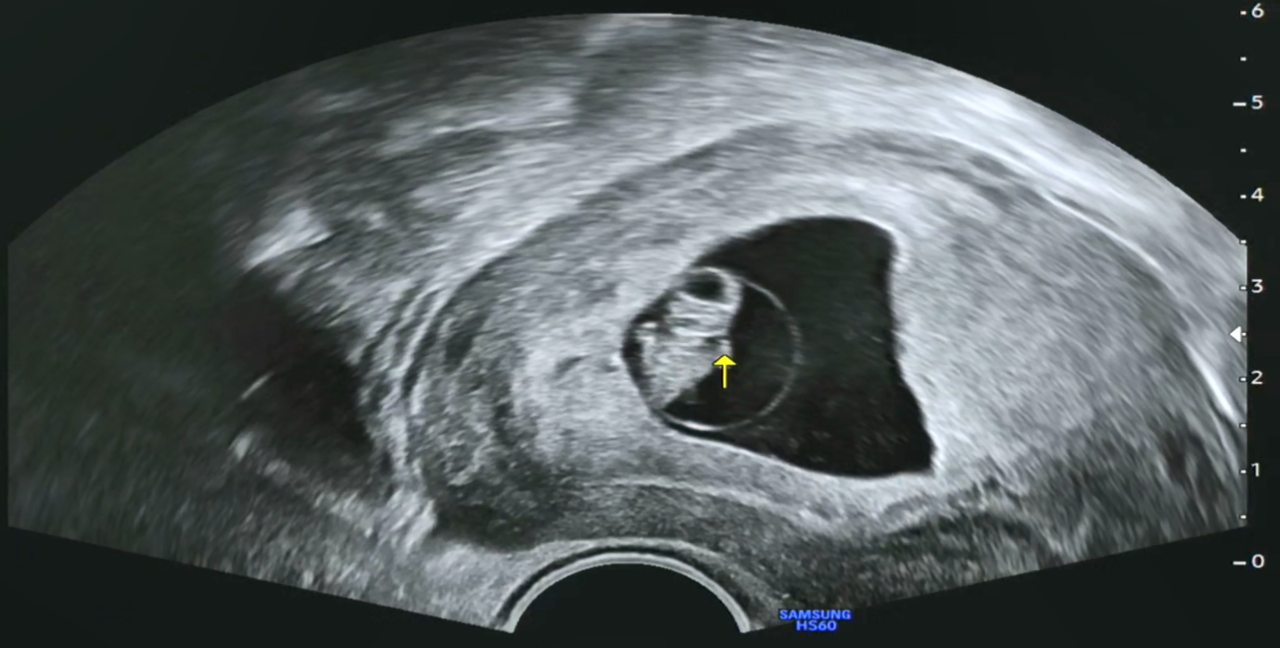

오전 10시쯤 되니 딸아이로부터 카톡을 통해, 우리 '팡팡이의 8주 0일 초음파' 동영상이 날아왔습니다.

임신 7~8주쯤 되면 기관의 형성기라고 해서 아기의 뇌와 몸의 기초가 만들어진다고 하고, 심장이 형성되면서 혈액이 몸으로 보내지기 때문에 심장을 확인할 수 있다고도 하네요.

임신 8주 차 아기의 크기가 1.5~1.6cm 정도로 성장한다고 하는데, 우리 '팡팡이'는 1.67cm라 딱 주수에 맞게 크고 있다고 하네요. 그리고 심장박동수도 점차 증가하여 9주까지는 160~180 bpm 정도라고 하는데, 현재 171 bpm이니 정상이라고 합니다(인터넷에서 검색해 보니 조금씩 다르게 수치가 나오기는 하더라고요).

오늘도 병원에서는 태아에게 무리가 된다고 심장박동음은 안 들려주었다고 합니다. 그래도 초음파 동영상을 보면 심장이 잘 뛰는 모습을 볼 수 있어서 마음은 놓입니다. 아마 다음 주 목 또는 금요일에 초음파를 통해 심장박동음을 듣고, 문제가 없으면 시험관시술을 한 병원에서 졸업(?)한다고 합니다. 그렇게 되면 집에서 가까운 산부인과 병원으로 전원 하여 출산까지 그 병원으로 다닌다고 하네요.

[팡팡이 8주 차 초음파 영상]